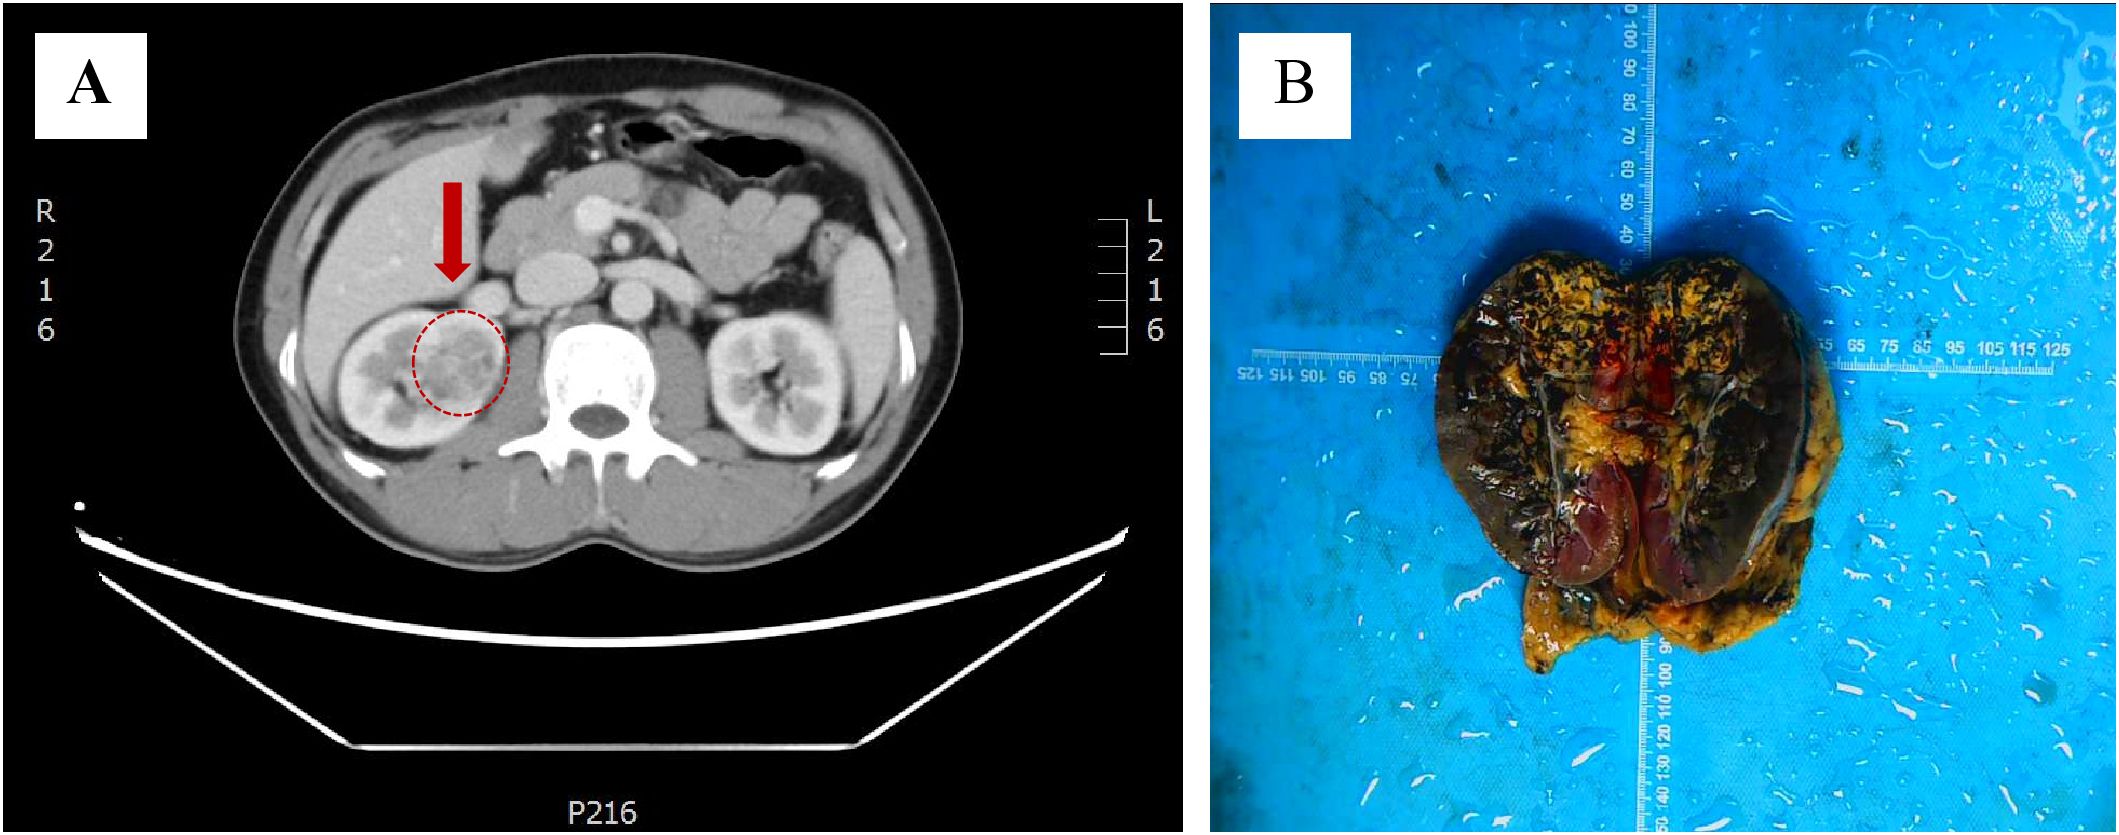

A 48-year-old man presented to the urology department with an incidentally discovered renal lesion on screening CT scan (Figure 1A), showing rounded nodular low-density shadows in renal parenchyma with a clear boundary, and uneven enhancement was observed on the enhanced CT scan. The TNM stage was observed to be stage I. The patient underwent radical nephrectomy and were followed up for 14 months without any other treatment after surgery. The case has survived till now and showed no evidence of recurrence or metastasis.

Figure 1. Discovery of ELOC(TCEB1)-RCC. (A) CT scans showed rounded low-density shadows in renal parenchyma. (B) Gross observation of ELOC(TCEB1)-RCC.

The tumor was located in the renal parenchyma, approximately 3.5 cm in diameter, nodular, gray-yellow or gray-brown, solid in texture and with clear boundaries (Figure 1B). All hematoxylin and eosin (H&E) slides from the case of ELOC(TCEB1)-RCC from Department of Pathology, The Second Xiangya Hospital, were reviewed by two experienced genitourinary pathologists. The tumor of the patient was nodular (Figure 2A); a thick fibrous pseudocapsule rich in smooth muscle was visible (Figure 2B). The tumor cells were mainly arranged in dense medium-sized acini (Figure 2C) or short papillae (Figure 2D). The tumor cells had clear boundaries, transparent cytoplasm, irregular or short fusiform nuclei, dense chromatin, unclear nucleoli, slight atypia, and WHO/ISUP nuclear grade 1 (Figure 2E). In the tumor of this patient, multifocal lymphocyte aggregation (Figure 2F, G) was observed, accompanied by hemorrhage and hemosiderin deposition (Figure 2H).

ELOC(TCEB1)-RCC was first reported in 2015, with more than 90% of patients being male (9). Most cases exhibit low-grade malignancy, but 10% of cases show metastasis. This case involves a 48-year-old male, with the tumor located in the right kidney and no metastasis observed (Figure 1). ELOC(TCEB1)-RCC has a broad morphological spectrum, mainly characterized by fibrous smooth muscle tissue separating the tumor into nodular structures (10). The tumor cells have clear cytoplasm and fibrous/fibromuscular stroma (FMS) (or leiomyoma-like stroma), making the tumor appear nodular under low-power microscopy. The architecture is diverse, including solid, acinar, and nested patterns, occasionally with cystic and tubulopapillary structures (11). Importantly, this tumor shows positive CK7 expression with significant variation—expression results differ in some tumors, with as low as 10% to 15% of tumor cells stained, ranging from patchy to diffuse. CA9 (typically with complete membranous staining) and CD10 are consistently immunoreactive. The positivity of CK7 and CA9 is typical and is required for the diagnosis of RCC with FMS (10). These morphological and immunological features are essential criteria for the diagnosis of ELOC(TCEB1)-RCC. The case is also characterized by fibromuscular tissue dividing the tumor into nodular shapes. Morphologically, it is characterized by branched acinar or tubular structures, with focal scattered short papillary structures (Figure 2). Immunologically, tumor cells are positive for CA9 and CK7, and ELOC shows nuclear positivity (Figure 3). Additionally, in this case, tumor cells don’t express CD117, TFE3, HMB45, or SDHB, but express FH and INI1(SMARCB1). Thus, we can exclude other molecularly-defined RCC categories, including TFE3-rearranged RCC, FH-deficient RCC, SDH-deficient RCC, and SMARCB1-deficient RCC.